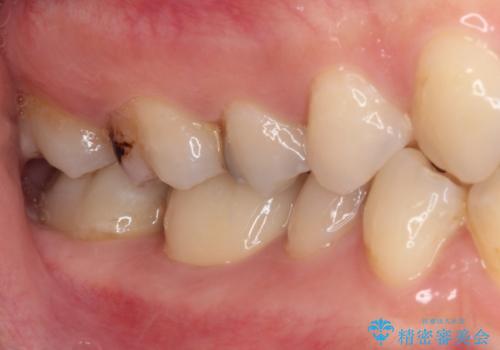

放置した虫歯 根管治療とオールセラミッククラウン

- 奥歯の虫歯を放置してしまい、痛みを感じることがあるとのことで来院された患者様です。

術前の診査では、神経を取り除かなくても済む可能性が示唆されましたが、実際に虫歯除去を進めたところ、レントゲン写真から読み取れる通り、神経組織にまで虫歯が及んでいることが分かりました。